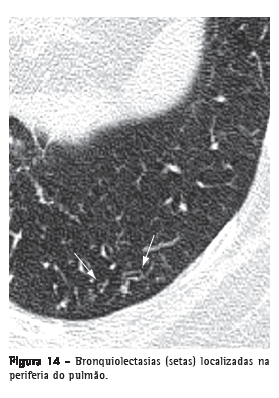

Bronquiolectasia

Dilatação bronquiolar. Análoga às bronquiectasias, mas em uma via aérea de muito menor calibre, identificada na periferia pulmonar (Figura 14). Manifestam-se como estruturas arredondadas ou tubulares, geralmente na periferia pulmonar, e com paredes espessadas ou preenchidas por secreção (ver Padrão de árvore em brotamento).(3,7) Também podem se associar a outras opacidades pulmonares e à distorção do parênquima em situações de fibrose.

Ver também Bronquiectasia e bronquiolectasia de tração.